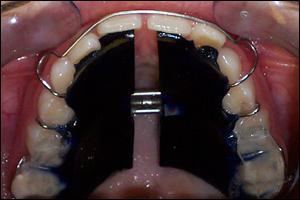

Fig 4: The Maxillary Twin Block

Fig 5: The Mandibular Twin Block